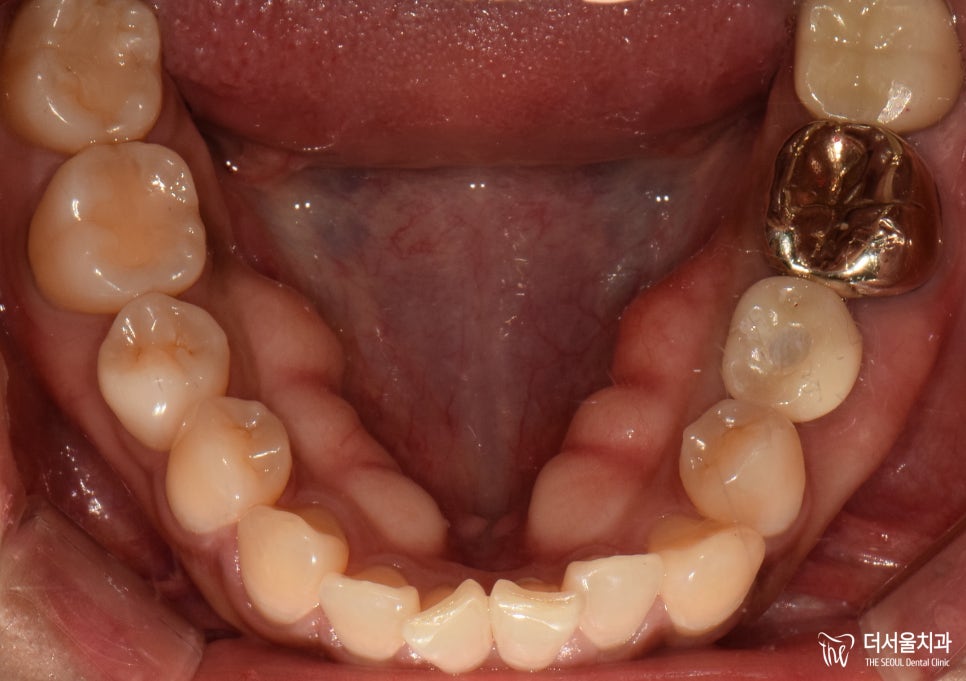

환자분 또한 역시 흔들림 증세가 없어져

한껏 편안해졌으며,

보철이 튼튼하게 자리를 잡게 되어

음식을 먹는데 한껏 더 편해졌답니다.